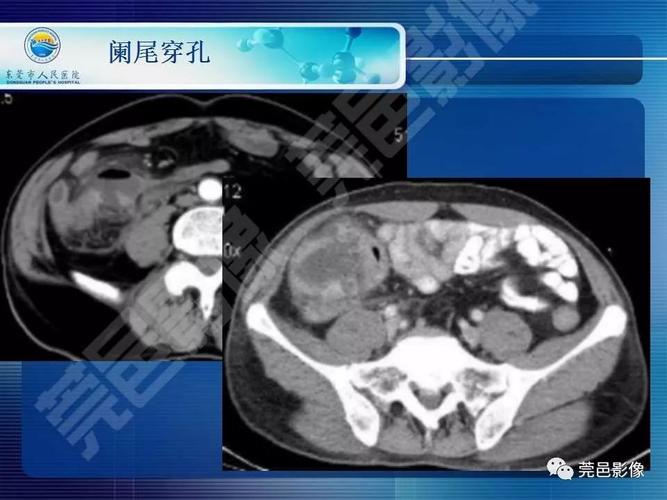

ct片上总是找不到阑尾3步法教你快速定位

急性阑尾炎的ct表现

【经典之作】正常阑尾和阑尾炎的ct表现

急性阑尾炎ct诊断

全面讲解正常阑尾和阑尾炎的ct表现